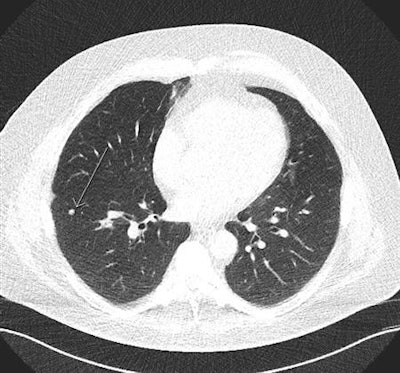

In this low-dose CT scan, the arrow points to a cancer in the left upper lobe.They examined the effects and costs of 648 screening scenarios with different screening start and stop ages, smoking eligibility criteria, and screening intervals from a public healthcare system perspective across a lifetime horizon in the simulated cohort.